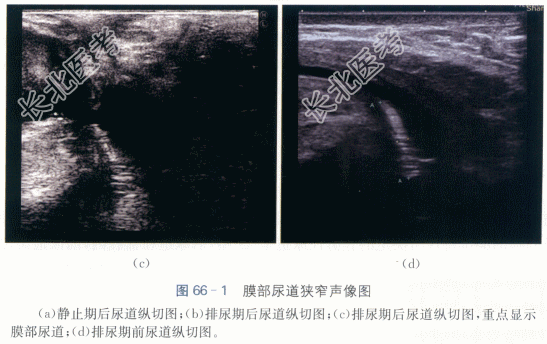

1.病史

患者,男性,32岁,因“后尿道重建术后2年,进行性排尿困难6个月”就诊。患者2年余前因外伤致骨盆骨折,膜部尿道断裂,于当地医院行急诊尿道会师术(具体不详),术后1个月拔出尿管后排尿尚可,在当地医院门诊间歇尿道扩张维持。近半年出现排尿困难,逐渐加重,1个月前出现尿滴沥,当地医院给予膀胱造瘘处理,患者为进一步诊治入院。

二、影像资料